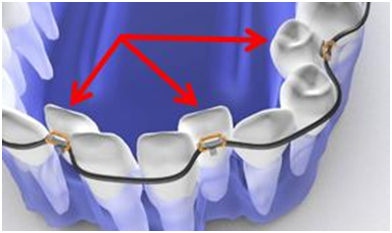

According to the Viazis Classification, malpositioned teeth that were typically referred to as crowding should now be referred to as alveolar bone hypoplasia. It's remarkable that orthodontic diagnosis has ignored the unique periodontal architecture of malpositioned teeth for over a century by merely referring to malpositioned teeth with terms like "crowding". It is the distinctive alveolar bone morphology (Figure 1) typically labial to the lingually displaced roots of anterior teeth that results in insufficient labial alveolar bone and associated soft tissue, edema, and erythema.

Figure 1 Malpostioned mandibular anterior teeth are characterized by their lingually displaced roots which results in insufficient labial alveolar bone and associated soft tissue, edema and erythema. Note the distinct cleft labial to the mandibular left lateral incisor.

The first case example (Figure 1) illustrates the severe malpositioned mandibular anterior teeth. These malpositioned mandibular anterior teeth are characterized by their lingually displaced roots resulting in insufficient labial alveolar bone and associated soft tissue, edema, and erythema. Note the distinct cleft labial to the mandibular left lateral incisor. The accompanying graphic representation (Figure 2) illustrates the clinical objectives of uprighting (i.e. red arrows) roots to reverse Orthodontosis ™ and eliminate Orthodontitis™.

Figure 2 Graphic illustration of severely malpositioned mandibular anterior teeth and clinical objectives of uprighting (i.e. red arrows) roots to reverse Orthodontosis™ and eliminate Orthodontitis™.